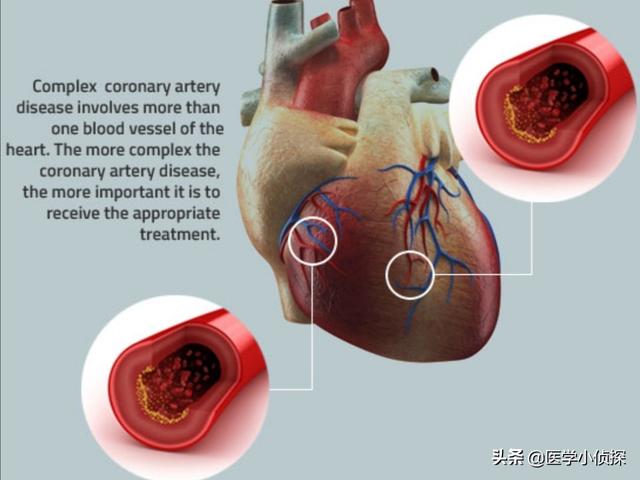

第二に、ステント治療を受けなかったとしても、冠動脈は非常に長い動脈で、多くの枝があります。ここが狭くないからといって、どこも狭くないとは限らない。アテローム性動脈硬化症は全身性の疾患であり、血管が1本でもあれば他の血管も同様に危険にさらされる。

(1) 冠動脈:冠動脈は心臓、すなわち心筋そのものに血液を供給する動脈である。 冠動脈には3本の太い幹があり、それが次第にさまざまな枝に漸増し、最終的には心臓と心筋組織全体に密な魚網を形成する。冠動脈疾患病変の大部分はこの3本の太い幹にあり、枝分かれの第一段階である小枝の病変は比較的小さい。臨床用語で "3枝病変 "とは、右冠動脈、前下行枝、エコー源性枝の3つの主幹を指す。

中国では、心血管疾患と脳血管疾患が住民の主な死因であり、冠状動脈性心疾患は心血管疾患の重要な一部である。中国における冠状動脈性心疾患の有病率と死亡率はともに増加傾向にあり、2017年、中国における冠状動脈性心疾患の死亡率は人口10万人当たり115.32人であった。

冠動脈疾患には多くの種類があり、プラークが安定しているか否かで慢性冠動脈疾患と急性冠症候群に分けられる。